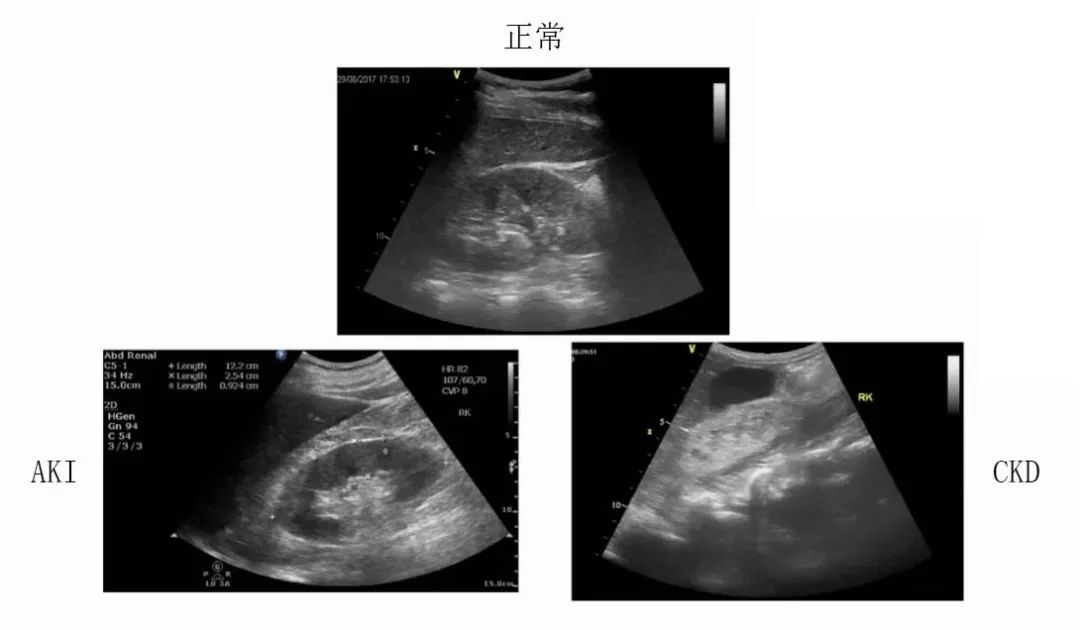

4.1个回声

正常情况下,肾脏回声应低于其周围组织(肝脏和脾脏)回声。 脾脏回声高于肝脏,因此,应以肝脏为参照。

肾脏正常回声与异常情况回声图